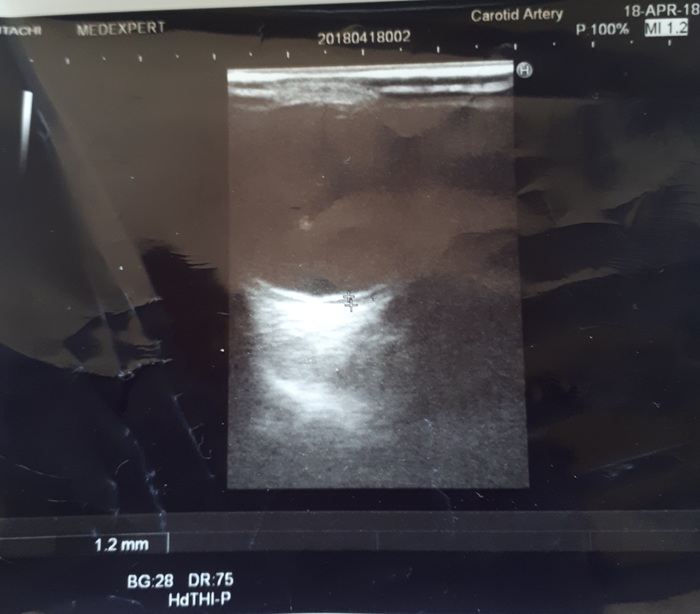

Я приехал на такси на консультацию в "Офтальмику" и получив атропин в глаза - на ОКТ поставили 100% диагноз - тракционный разрыв сетчатки. Как и предпологалось - разрывной клапан снизу - расположен на 7часов - типичный травматический разрыв, так назывемый - "почесабельный" - возникает чаще всего, когда глаз грубо пытаются почесать пальцем снизу - типично для тех, у кого "пыльная" работа.

Отслоение сетчатки почти до макулы. Дегенеративные изменения по периферии, очаги ретиношизиса... Второй глаз может рвануть так же - в любой момент, потому, что у меня миопия высокой степени. С 8 лет ношу очки минус 7,0 на оба глаза. А это 99% предрасположенность к разрывам сетчатки. И я за свои 45лет не сном, не духом даже не предполагал о том, что такое вообще возможно. Короче полный Аминь!